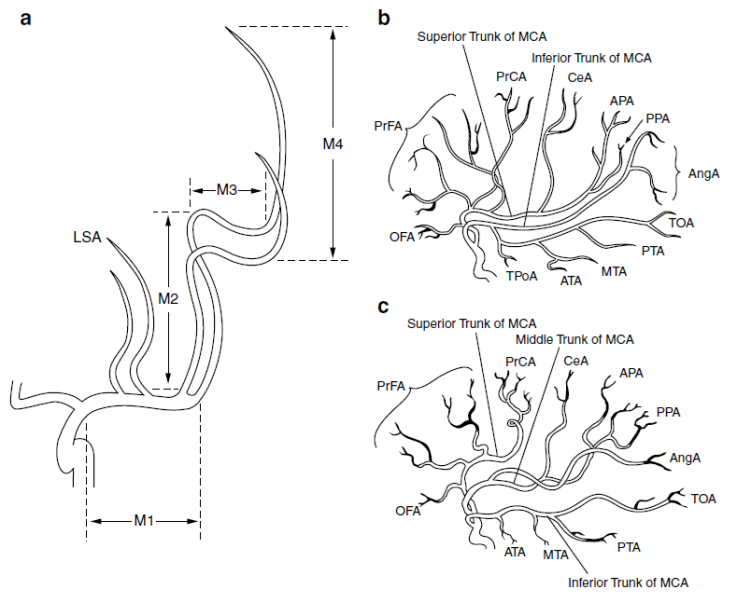

Middle

cerebral artery

(From Neurovascular imaging –

2011)

MCA divides in 3 patterns:

·

Bifurcation into

superior and inferior divisions (78%) – (b)

·

Trifurcation into

superior, middle inferior (12% - (C)

·

Division into

multiple divions

Recurrent Artery of

Heubner – can have variable origin

before or after A1/A2 junction